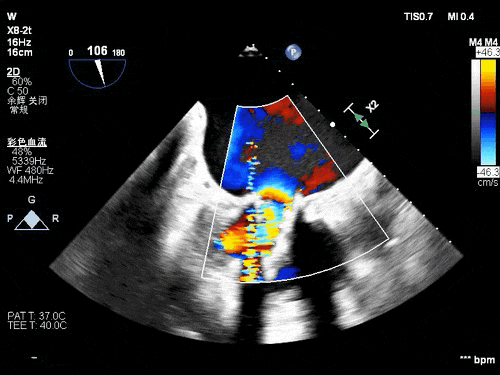

术前TEE影像

术后TEE图像

瓣膜释放后超声观察无瓣周漏,峰值流速0.76m/s,峰值压差5mmHg,平均压差2mmHg,流出道峰值流速1.28m/s,峰值压差7mmHg。